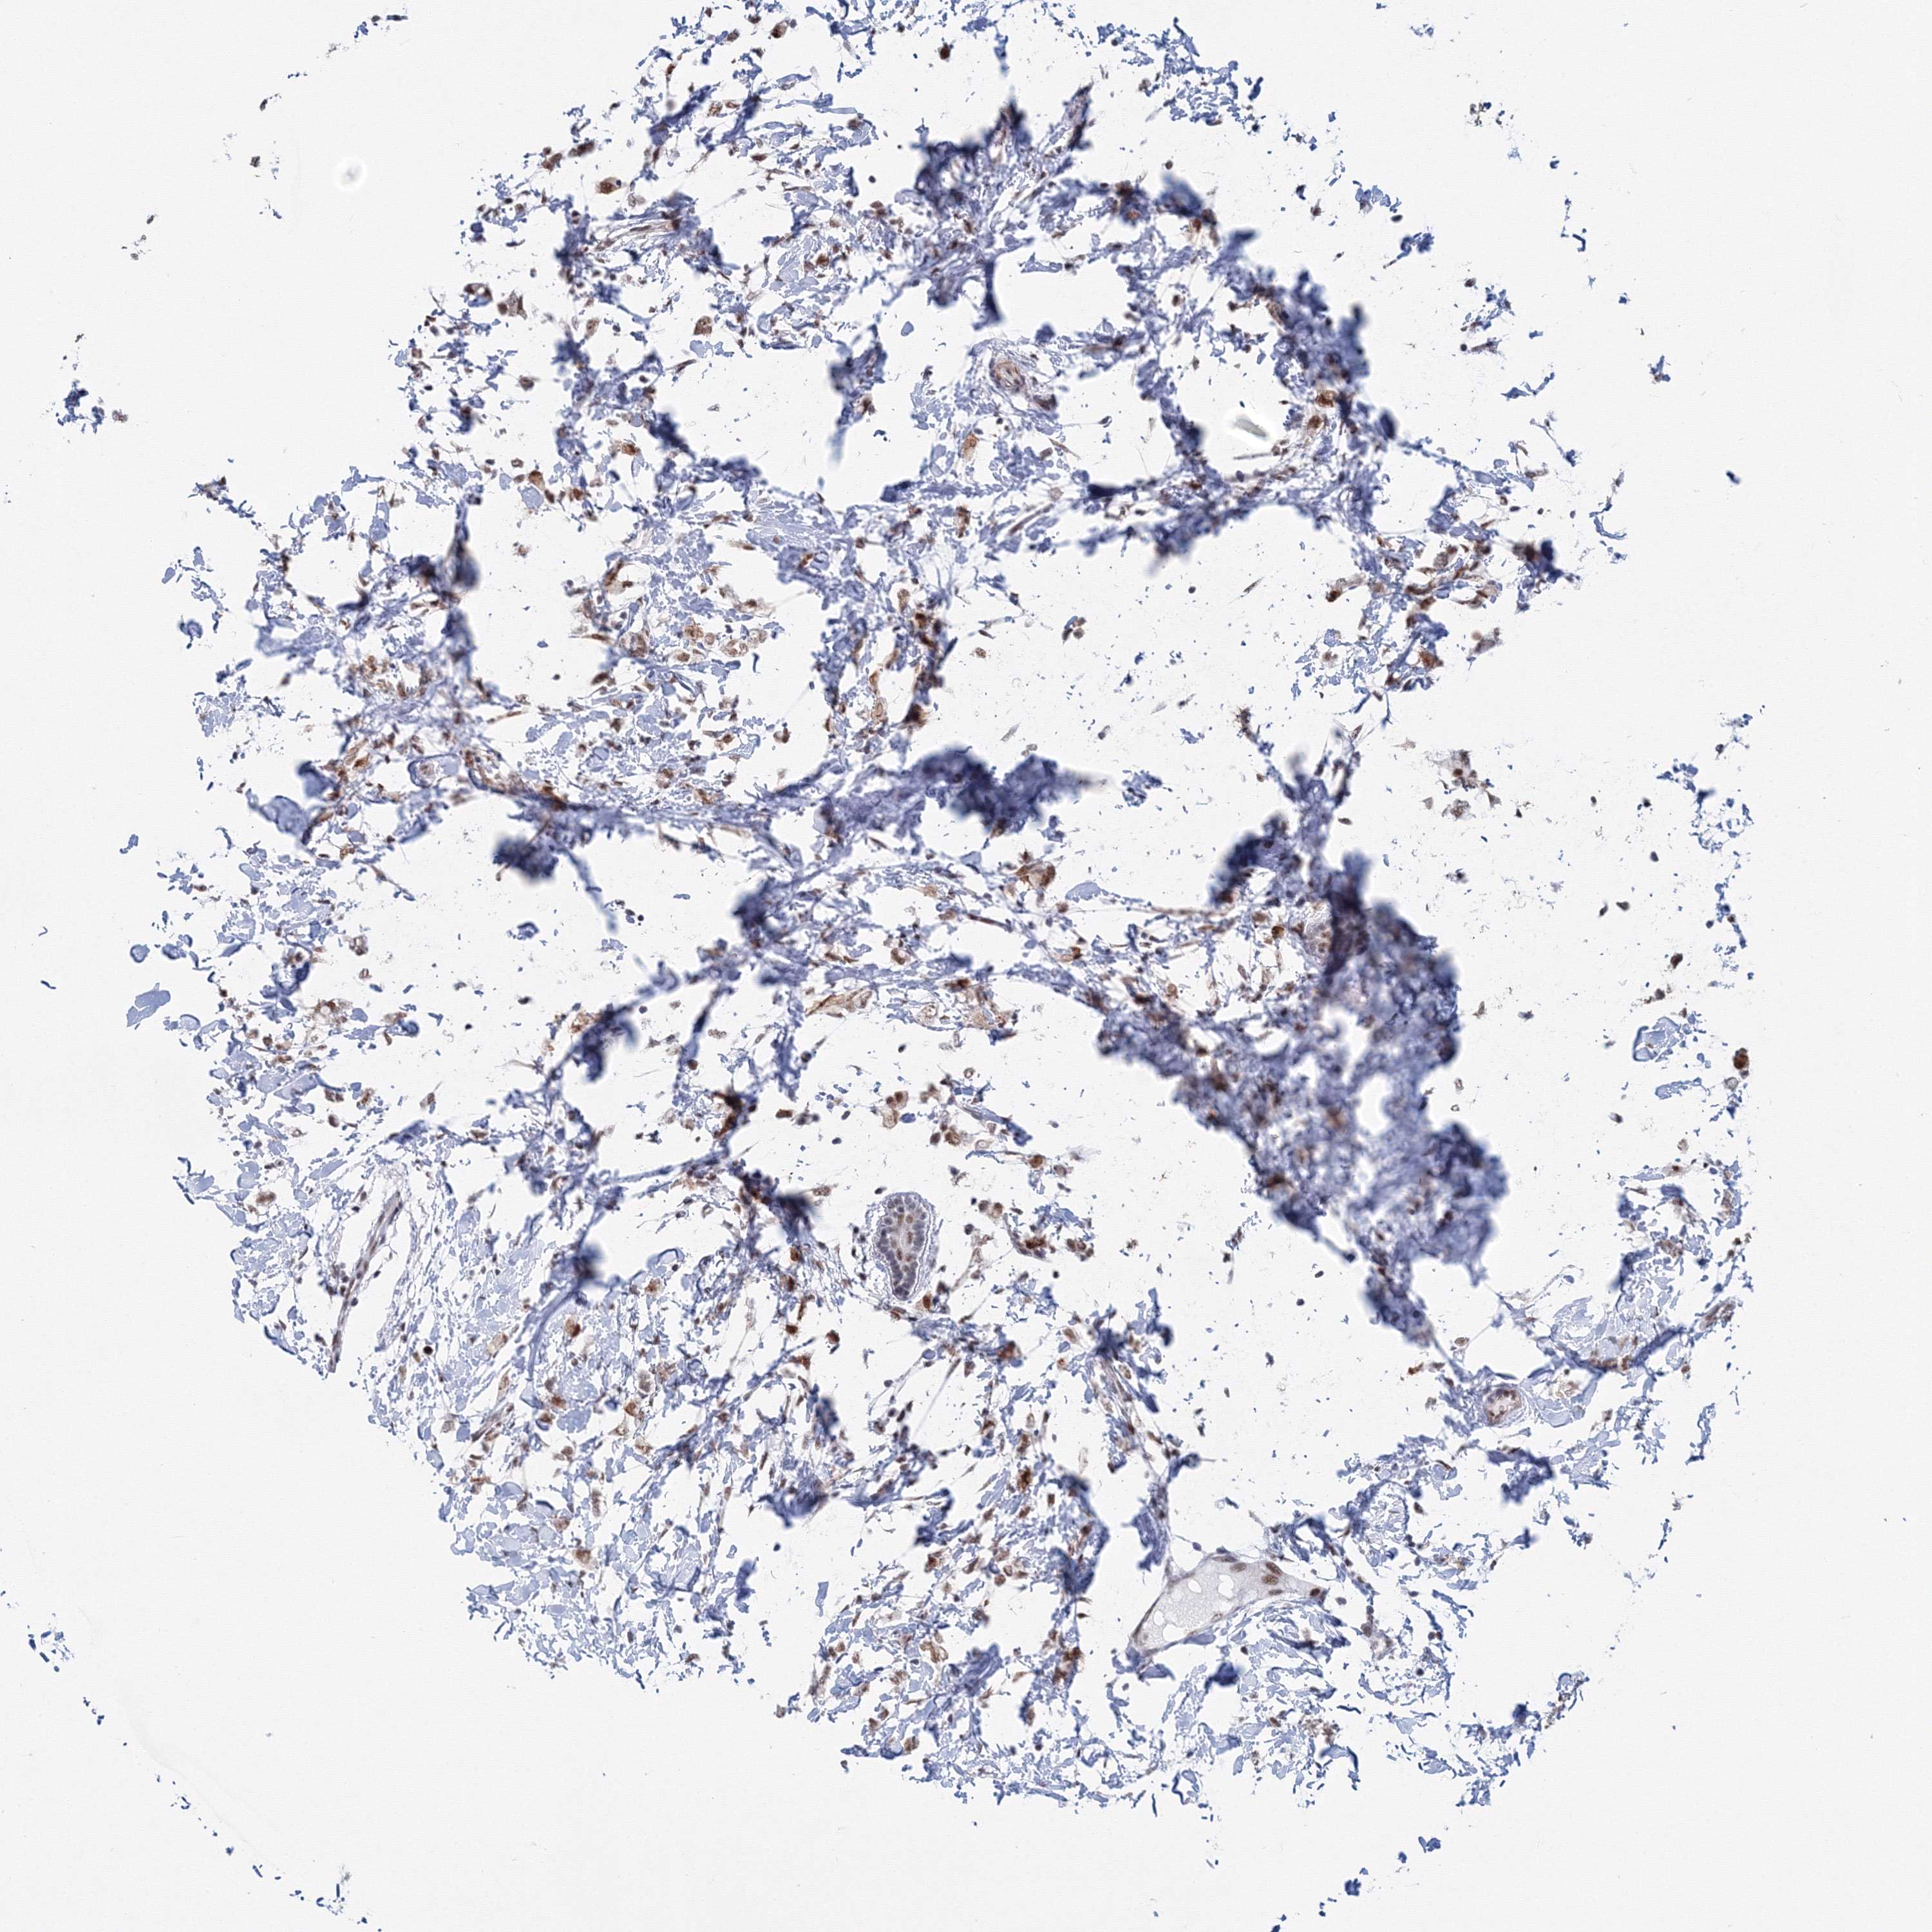

CANCER BREAST CANCER Show tissue menu

BRCA TCGA BRCA VALIDATION PROTEIN EXPRESSION

ANTIBODIES

AND

VALIDATION